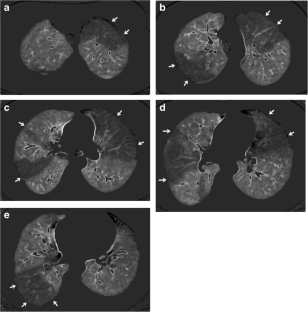

Fig. 1

Fig. 2